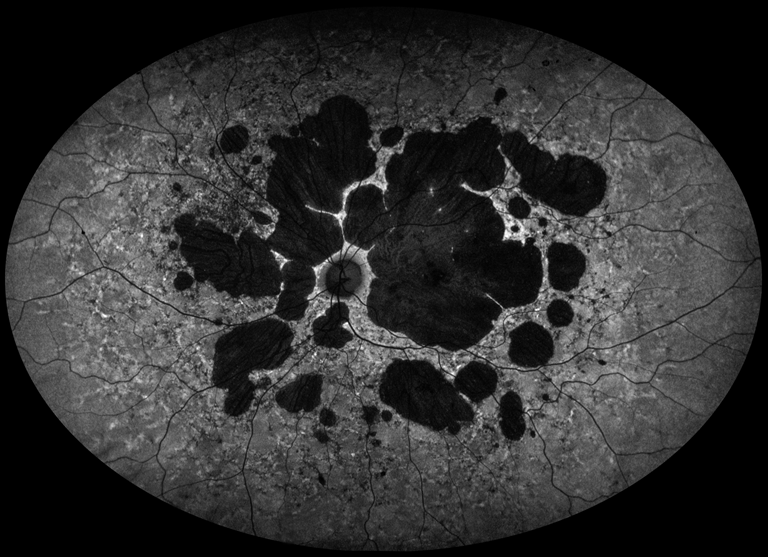

Stargardt Disease

Presented by Judith Gulian, BSc, OCT-CThis photograph received 1st Place in the category "Fundus Autofluorescence" and was displayed at the 2024 ASCRS/OPS Society Exhibit.